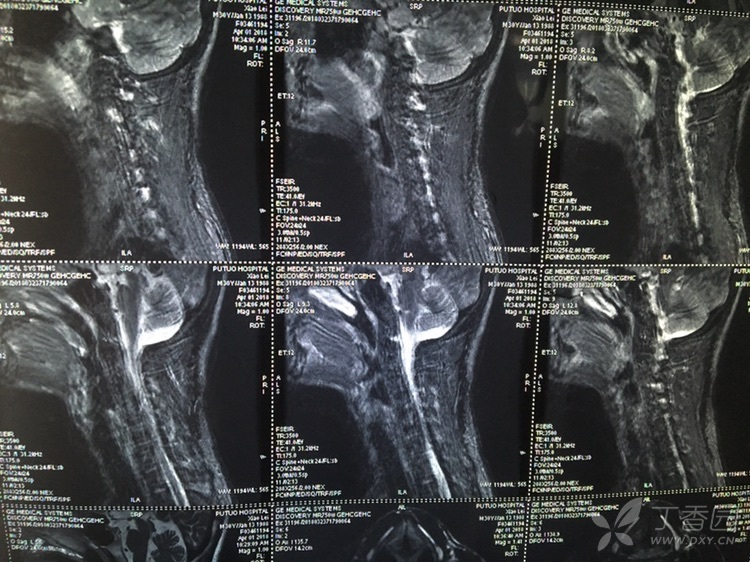

Feb 26, 21 · 颈椎压迫神经的症状分为压迫神经根和颈髓两方面。 颈椎压迫神经根的症状有:1、疼痛,一般表现为自颈部向上肢的放射性疼痛;2、感觉障碍,受到压迫神经根在上肢的支配区出现麻木、痛觉过敏、感觉减退等症状;3、肌力改变,早期肌张力亢进,晚期肌张力减弱,肌肉出现萎缩。Nov 08, 11 · 颈椎病吃药只是缓解作用,要除根的话建议您还是接受正规的治疗,最好是保守治疗,您与眩晕的情况的话应该属于脊髓型的,最好不要再耽误了,我们是通过中医手法复位正骨后(正骨12周,每隔一天一次,30分钟每次)改变压迫神经的关节位置使其不再压迫Aug 23, 19 · 虽然说确实有压迫神经的可能,但依然只是猜测,目前已有的检查并不能确诊! 患者需要做一个颈部核磁,这个检查是很有必要的,不光是确诊,更是未来治疗的依据,我们需要通过核磁更为详细的了解患者病情,病变位置、神经压迫程度进行综合考虑,对于此类患者来说,治疗方式有很多,作

May 18, 12 · 全部症状:手指没力肌肉萎缩 发病时间及原因:12年5月 治疗情况:先想咨询一下还没治有后遗症吗?,Apr 12, 17 · 颈椎病症状主要是由于神经受压引起的,那么治疗关键就在于解除对神经的压迫。 开刀手术是其中的一种的方法但是该病属于退行性疾病,一般情况下建议先配合保守治疗。Sep 26, 18 · 由于颈椎疾病病变导致的压迫神经,从而引发的神经激惹和神经损伤症状,应该属于神经根型颈椎病,应该针对这种神经损伤症状做系统的治疗。 首先,要做颈椎的电动牵引,配合微波理疗、活血化瘀药物治疗,并且可以使用甘露醇脱水治疗,同时可以口服甲钴胺片剂做神经营养治疗。